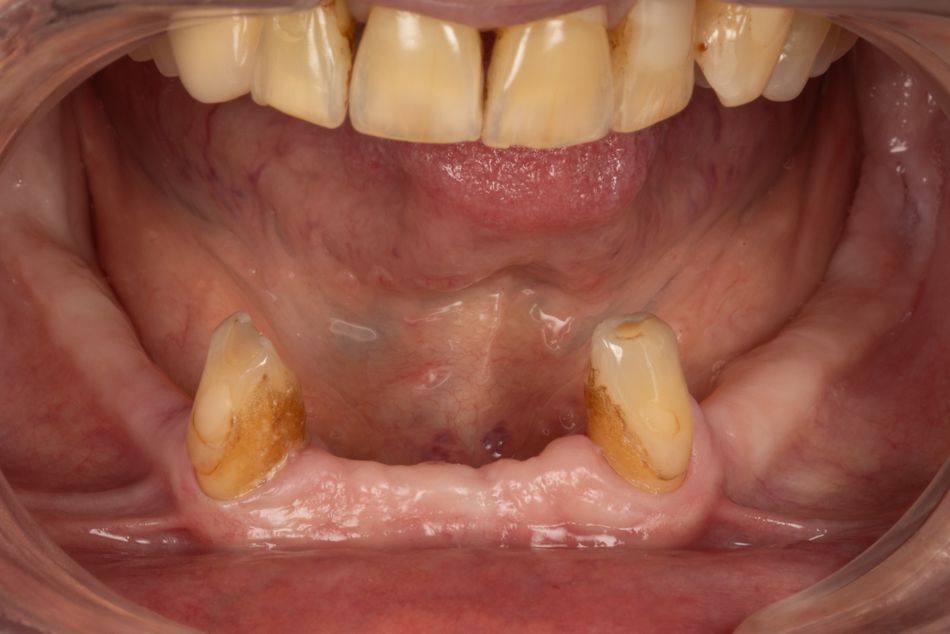

2c. Situation in the mandible: thin alveolar crest and residual teeth 33 and 43.

2c

A 70-year-old female patient in good general health but with a history of periodontal disease was referred to find a more durable solution for her mandible. The two remaining canines were mobile (mobility grade 1 for 33 / mobility grade 3 for 43) and supported an unstable Stellite restoration that was causing the patient pain.

Clinical and radiological examination revealed terminal periodontal disease on tooth 43 and advanced periodontal disease on tooth 33. The adjacent bone volume was adequate vertically, but the residual alveolar ridge was thin due to previous extractions (5 mm vestibulo-lingually on average). Periodontal cleaning was performed, and the soft tissues were healthy. Keratinised tissue was present throughout the residual alveolar ridge with a thickness greater than 1 mm.